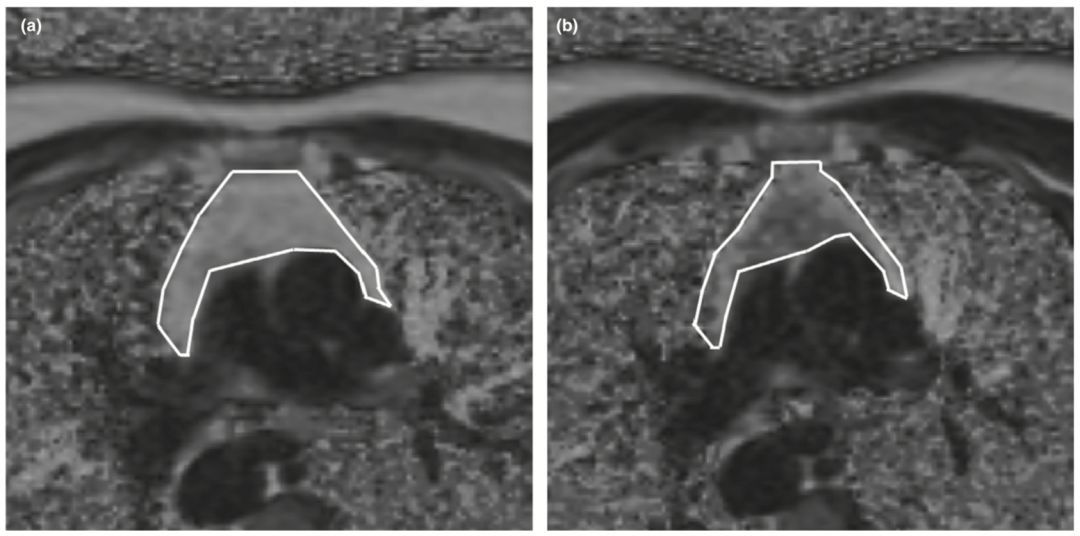

而且發起人人體免疫學家Gregory Fahy發現服用生長激素使得胸腺再生了,這可以恢復T細胞輸出,提高免疫力……

不過胸腺再生的圖片倒是和我先前在環球科學看到過的一樣。